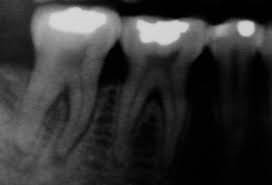

El problema puramente bacteriano de un tratamiento de conductos es solucionable debido al perfeccionamiento de técnica y procedimientos. Esto lo comprueban los éxitos obtenidos por verdaderos artistas en la materia. Se ha visto inclusive que en relativamente corto tiempo, después de un tratamiento de conductos, se normaliza la estructura ósea que presentaba alteraciones comprobadas radiográficamente en terreno periapical. Controles radiográficos repetidos han demostrado lo dicho hasta la saciedad. No obstante tengo que responderle a los que dicen que el tratamiento de conductos perfecto – y les aseguro que no dudo que estas endodoncias existen- es la mejor terapia focal dentógena, que esto en ningún caso equivale a un “saneamiento focal” si efectúan una endodoncia ideal y creen que con ello hicieron un saneamiento focal, están en el error (Raab, 1964) y este error se debe a un mal entendido en la nomenclatura, pues hemos visto que dichos autores (verdaderos expertos en su oficio) entienden por “foco” la alteración periapical radiográficamente visible (el granuloma), mientras que nosotros bajo”foco” tomamos en correcta consecuencia a lo dicho, todo el diente con pulpa muerta, así sea que se presente ahora una curación morfológica reconocible de su osteitis periapical sigue en la boca interfiriendo como “foco intradental” Es también el motivo por el cual rechazamos la amputación apical como terapia focal dentógena.

Pritz (1956) se dio el trabajo de valorar 1000 historias clínicas del año 1952 de pacientes hospitalizados que fueron referidos al departamento clínico de odontología de Altmann. Este material representa sin duda alguna un promedio amplio que alcanza a dar datos suficientes sobre el cuidado dental de toda la población. A 760 pacientes se les hizo una investigación completa clínica y radiológica tanto de la dentadura como de la región maxilomandibular. De 13.546 dientes examinados se encontraron a ala evaluación clínica y radiológica 2.717 con pulpa muerta, lo que equivale a un 20%, cifra que por paciente da un promedio de 3.6 dientes muertos. De los 717 dientes con pulpa muerta se le encontró a 1.887 (69.4) alteraciones radiológicas. De todos los dientes con pulpa muerta habían recibido tratamiento de conducto 1.836 y de éstos presentaban 1.194 (65%) alteraciones radiológicas.

Respecto al alto porcentaje de las alteraciones radiográficas visibles, anota Pritz que entre ellas se encuentran tanto las conocidas alteraciones de la osteitis apical crónica, como ensanchamientos claros y clásicos del espacio periodontal, especialmente aquellos limitados a la parte apical. En aquel entonces F. Proell llamó la atención sobre el hecho de que dichos dientes, en su mayoría, había que considerarlos como infectados. En dientes con pulpa muerta de ubicación solitaria y en aquellos que se hallaban al final de una fila de dientes se encuentra el espacio periodontal de todas maneras ensanchado, debido a las alteraciones en la presión y a los cambios que sufre allí por sobrecarga de masticación. Pues bien, dichas alteraciones no se tuvieron en cuenta para la elaboración del trabajo. Solo se valoraron en ellos las alteraciones apicales. De estas juiciosas investigaciones hemos tenido que concluir que los portadores de dientes con pulpa muerta con o sin tratamiento de conductos, con o sin alteraciones radiológicas comprobables, presentan una morbidez elevada.